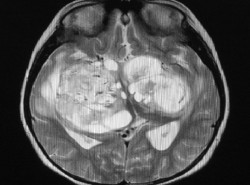

Un nuevo descubrimiento cuestiona la teoría predominante para tratar el Alzheimer

Un estudio dirigido por la Universidad de Cincinnati, en Estados Unidos, en colaboración con el Instituto Karolinska de Suecia, afirma que el tratamiento de la enfermedad de Alzheimer podría residir en la normalización de los niveles de una proteína cerebral específica llamada péptido beta-amiloide. Esta proteína es necesaria en su forma original y soluble para mantener el cerebro sano, pero a veces se endurece formando "piedras cerebrales" o cúmulos, llamados placas amiloides.